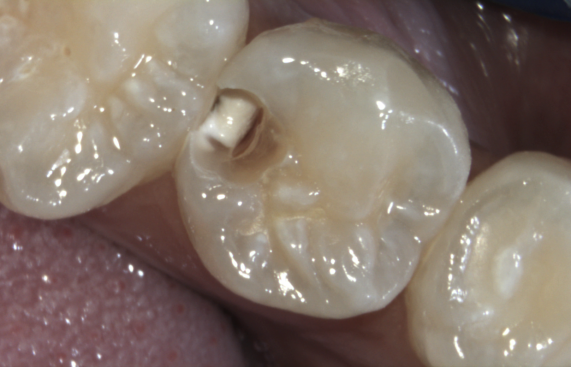

Befund: versteckte Zwischenraum-Caries am Backenzahn

unsichtbare<br />

Zwischenraum-Caries

unsichtbare